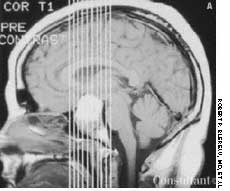

A 29-year-old woman is brought to the emergency department after a caraccident. She complains of head pain and has a contusion over the posterioraspect of the right temporal bone and right occipital bone; a small amount ofblood flows from the right external auditory canal. She has only a vague recollectionof the accident. Past medical history-although difficult to ascertain-seems noncontributory.